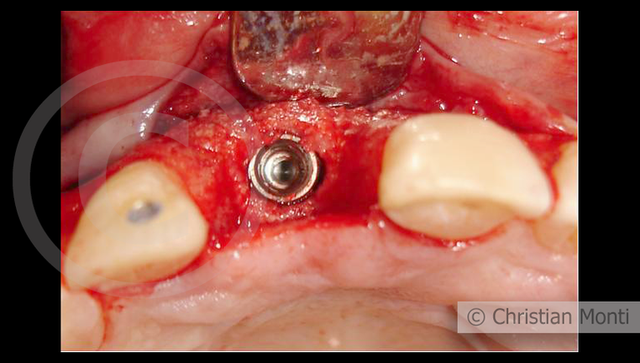

EDENTULIA SINGOLA

Impianto in sostituzione di un incisivo superiore